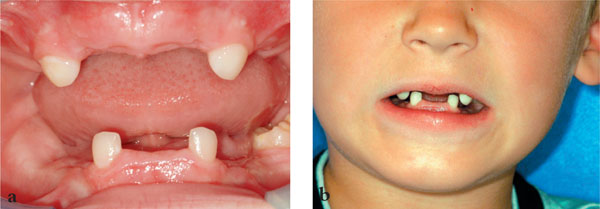

Fig 1-4 Child who has had multiple teeth extracted (a) intra-oral view and (b) extra-oral view.